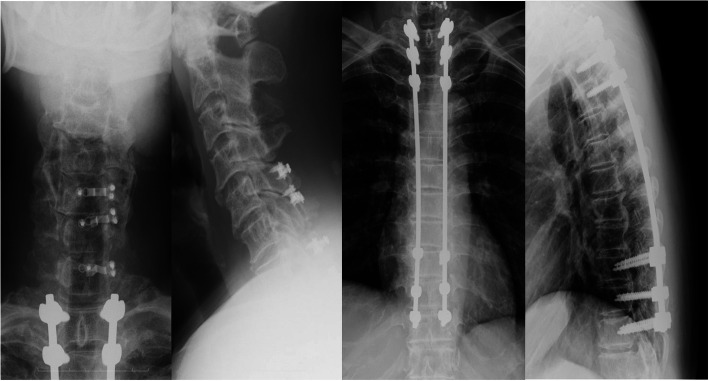

The neurological findings suggested spinal cord lesions below the T10 level, and T6/7 was judged to be the location of the primary lesion. T1–3 and T6–11 laminectomy and T1–11 posterior fixation were performed. Additionally, there was severe spinal cord compression in C6/7, and open-door laminoplasty with a lamina plate was performed for C5–7 (Fig. 5).

Fig. 5.

Postoperative cervical and thoracic lateral X-ray images. T1–3 and T6–11 Laminectomy and T1–11 posterior fixation were performed. And also, C5–7 open-door laminoplasty was performed with lamina plate